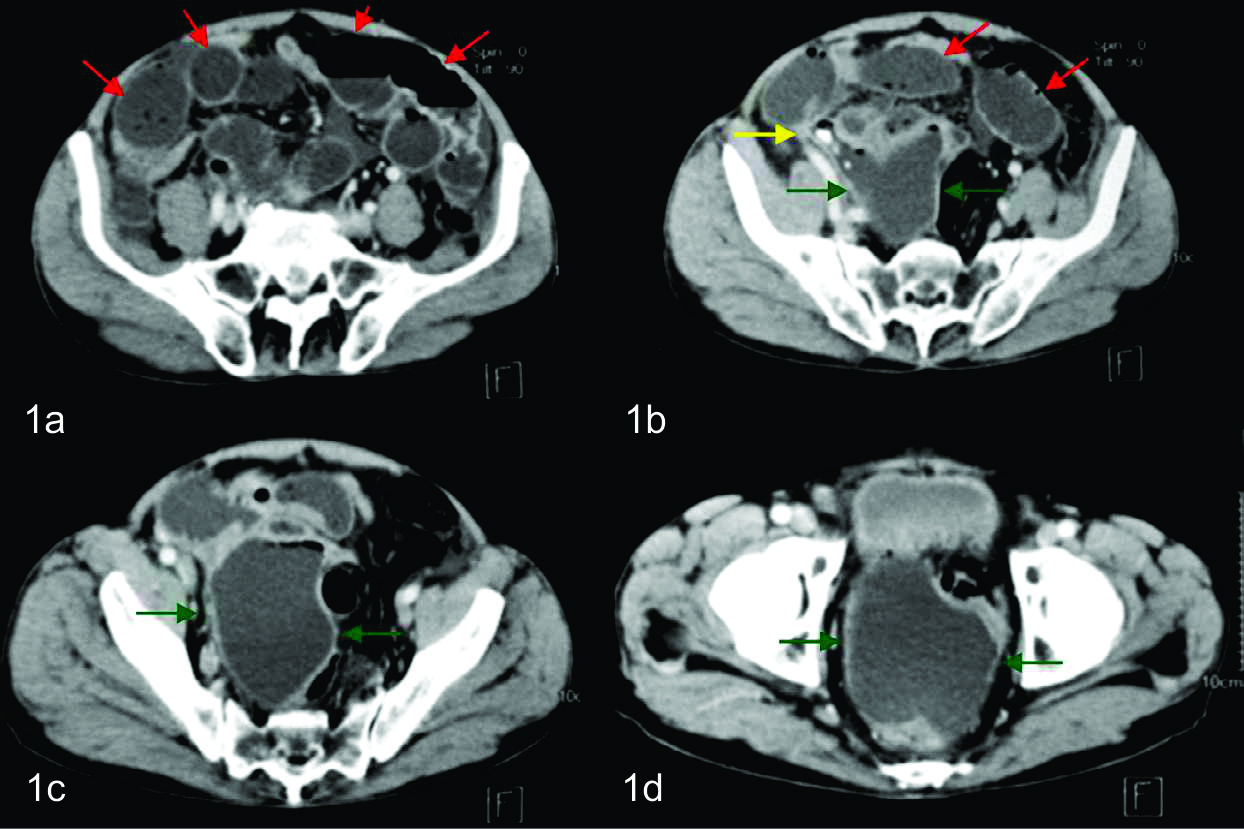

Se le realizo TC con Medio de contraste intravenoso (MC i/v) en fase portal , apreciándose asas intestinales distendidas, algunas de ellas con niveles hidro-aereos en su interior. Se observa además a nivel de la pelvis, con epicentro en el fondo de saco de Douglas una colección redondeada, bien definida, de paredes finas y regulares con contenido hipodenso.

La misma, por su sector superior derecho se extendía hasta la fosa iliaca reconociéndose a dicho nivel tres pequeñas imágenes calcicas redondeadas, que fueron interpretadas como apendicolitos, elemento semiológico fundamental, para arribar al diagnóstico de apendicitis aguda complicada con absceso pelviano. Con dicho planteo diagnostico se discute junto con los cirujanos de guardia tratantes la posibilidad de realizar manejo percutáneo del absceso como tratamiento inicial, y determinan en la evolución la eventualidad de realizar cirugía definitiva. El procedimiento fue realizado bajo guía tomográfica con el paciente en decúbito supino, Se valoro ventana de acceso y se procedió a topografiar el sitio de abordaje en piel, que fue a nivel de hipogastrio. Se procedió a colocar el drenaje bajo técnica de Trocar, utilizándose un drenaje multipropósito 14 F. El mismo se dejó abierto a bolsa colectora con llave de tres vías. El material obtenido fue francamente purulento y se tomaron muestras del mismo para análisis bacteriológico, cultivando flora polimicrobiana.

En el control tomográfico posterior, realizado a los 7 días del procedimiento, se reconoce el catéter de drenaje ingresando por la pared anterior del abdomen, el cual se dirige caudomedial con su extremo en el fondo de saco de Douglas, sin evidencia de colección residual. Se decide realizar prueba terapéutica cerrando el drenaje. Dada la buena evolución, el mismo es retirado a las 48 hs.

En la adquisición inicial se identifica una colección de paredes finas a nivel de fosa iliaca derecha, en relación a la raíz del mesenterio, inmediatamente por delante de los grandes vasos. La misma presentaba gas en el sector no declive y alteración de la densidad de la grasa adyacente, de aspecto inflamatorio.

En los cortes más caudales se reconoce al ciego en su topografía habitual y de él se observa emerger de su pared posterior, al apéndice cecal, el cual es de aspecto patológico, tomando contacto con la colección antes descripta. Con el planteo de apendicitis aguda complicada con colección infectada se discute junto con cirujano tratante la eventual posibilidad de poder realizar tratamiento percutáneo, el cual se determinó que era pasible de ser efectuado en este paciente. Se realizó nuevamente bajo guía tomográfica con el paciente en decúbito supino. Se procedió a topografiar el sitio de abordaje en piel a nivel de flanco derecho y se coloco drenaje multipropósito 12 F bajo técnica de Seldinger, el cual se dejo abierto a bolsa colectora con llave de tres vías. El material obtenido fue purulento, algo hemorrágico, con grumos, del cual se tomaron muestras para análisis bacteriológico, cultivando gérmenes gram negativos. En el control tomográfico posterior, a los cinco días de colocado el drenaje, se necesitó un reposicionamiento del mismo, pudiendo evacuar totalmente la colección residual en la evolución. Luego de 15 días de colocado el drenaje, con levados diarios en los últimos 7 días, una vez resuelta la colección, sin elementos clínicos ni paraclínicos humorales de infección, se decide retirar el drenaje, presentando el paciente una excelente evolución.